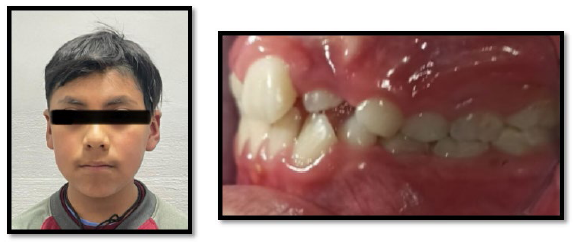

Paciente de 8 años de edad de sexo masculino, acude a la clínica odontológica acompañado de su mamá, solicitando tratamiento de ortodoncia. Al examen clínico extraoral se evidencia en una vista frontal simétrico sin alteraciones; en el examen clínico intraoral se evidencia un aumento de volumen entre las piezas 2,2 y 6,3, el mismo que mide aproximadamente 2 mm de ancho por 3 mm de largo, a la palpación de consistencia dura, mucosa adelgazada, color blanquecino y asintomático (Figura 1).

Figura 1: Fotografía extraoral e intraoral se observa la mucosa adelgazada y blanquecina por la presencia del incisivo suplementario.